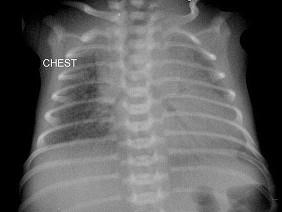

问题 早产儿,男,生后12小时,生后8小时出现呼吸困难,如图,最可能的诊断为?(?)

选项 A.新生儿肺炎 B.新生儿湿肺 C.新生儿肺出血 D.新生儿特发性呼吸窘迫综合症 E.胎粪吸入综合征

答案 D